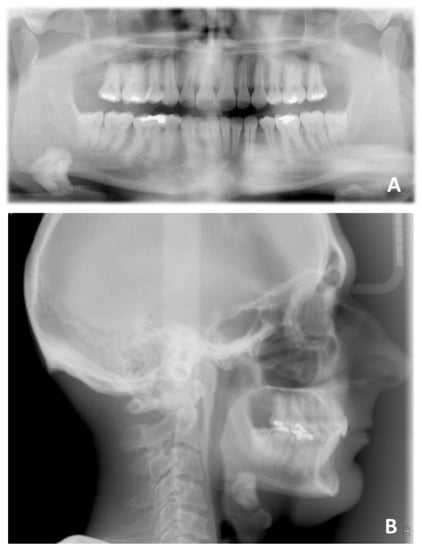

Figure 10. Pre-treatment radiographic of case number 1: (A) orthopantomography; (B) lateral cephalogram.

3. Case Report Number 1

The first case reported was an adult male patient who had already undergone orthodontic treatment in the past with the extraction of the four first premolars. The orthodontic situation (Figure 9, Figure 10 and Figure 11 and Table 1) showed a dentoskeletal class II malocclusion, upper and lower crowding, severe deep bite with impingement of the lower incisors on the palate, retroclination of the upper and lower incisors, and convex and biretruded profile. The patient was strongly brachyfacial, and therefore, a deep bite was not only dental but also skeletal. The patient showed good exposure of the upper incisors; therefore, in the resolution of the deep bite, it was preferable not to intrude upper incisors in order not to worsen the patient’s aesthetics.